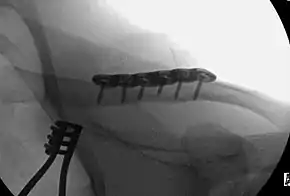

Surgery

For breaks in the middle of the clavicle in children surgery resulted in faster recover but more complications.[10] If the fracture is at the lateral end, the risk of nonunion is greater than if the fracture is of the shaft.[11] The evidence for different types of surgery for breaks of the middle part of the clavicle is poor as of 2015.[12]

A meta-analysis of midshaft clavicle fractures supports primary plate fixation of completely displaced midshaft clavicular fractures in active adults.[13]

A discontinuity in the bone shape often results from a clavicular fracture, visible through the skin, if not treated with surgery. Surgical procedures often call for open reduction internal [plate] fixation where an anatomically shaped titanium or steel plate is affixed along the superior aspect of the bone by several screws. In some cases, the plate is removed after healing due to discomfort, to avoid tissue aggravation, osteolysis or subacromial impingement. This is especially important with a special type of fixation plate called hook plate.[15] With anatomical plates plate removal is considered an elective procedure that is rarely necessary. An alternative to plate fixation is elastic TEN intramedullary nailing. These devices are implanted within the clavicle's canal to support the bone from the inside. Typical surgical complications are infection, neurological symptoms distal the incision (sometimes to the extremity), and nonunion of the bone (failure of the bone to properly fuse together).